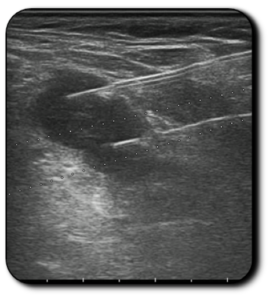

US image showing two fibres inside the lymph node

CEUS image showing the absence of enhancement after the treatment

Images courtesy of Dr. Giovanni Mauri (IEO Hospital, Milan)